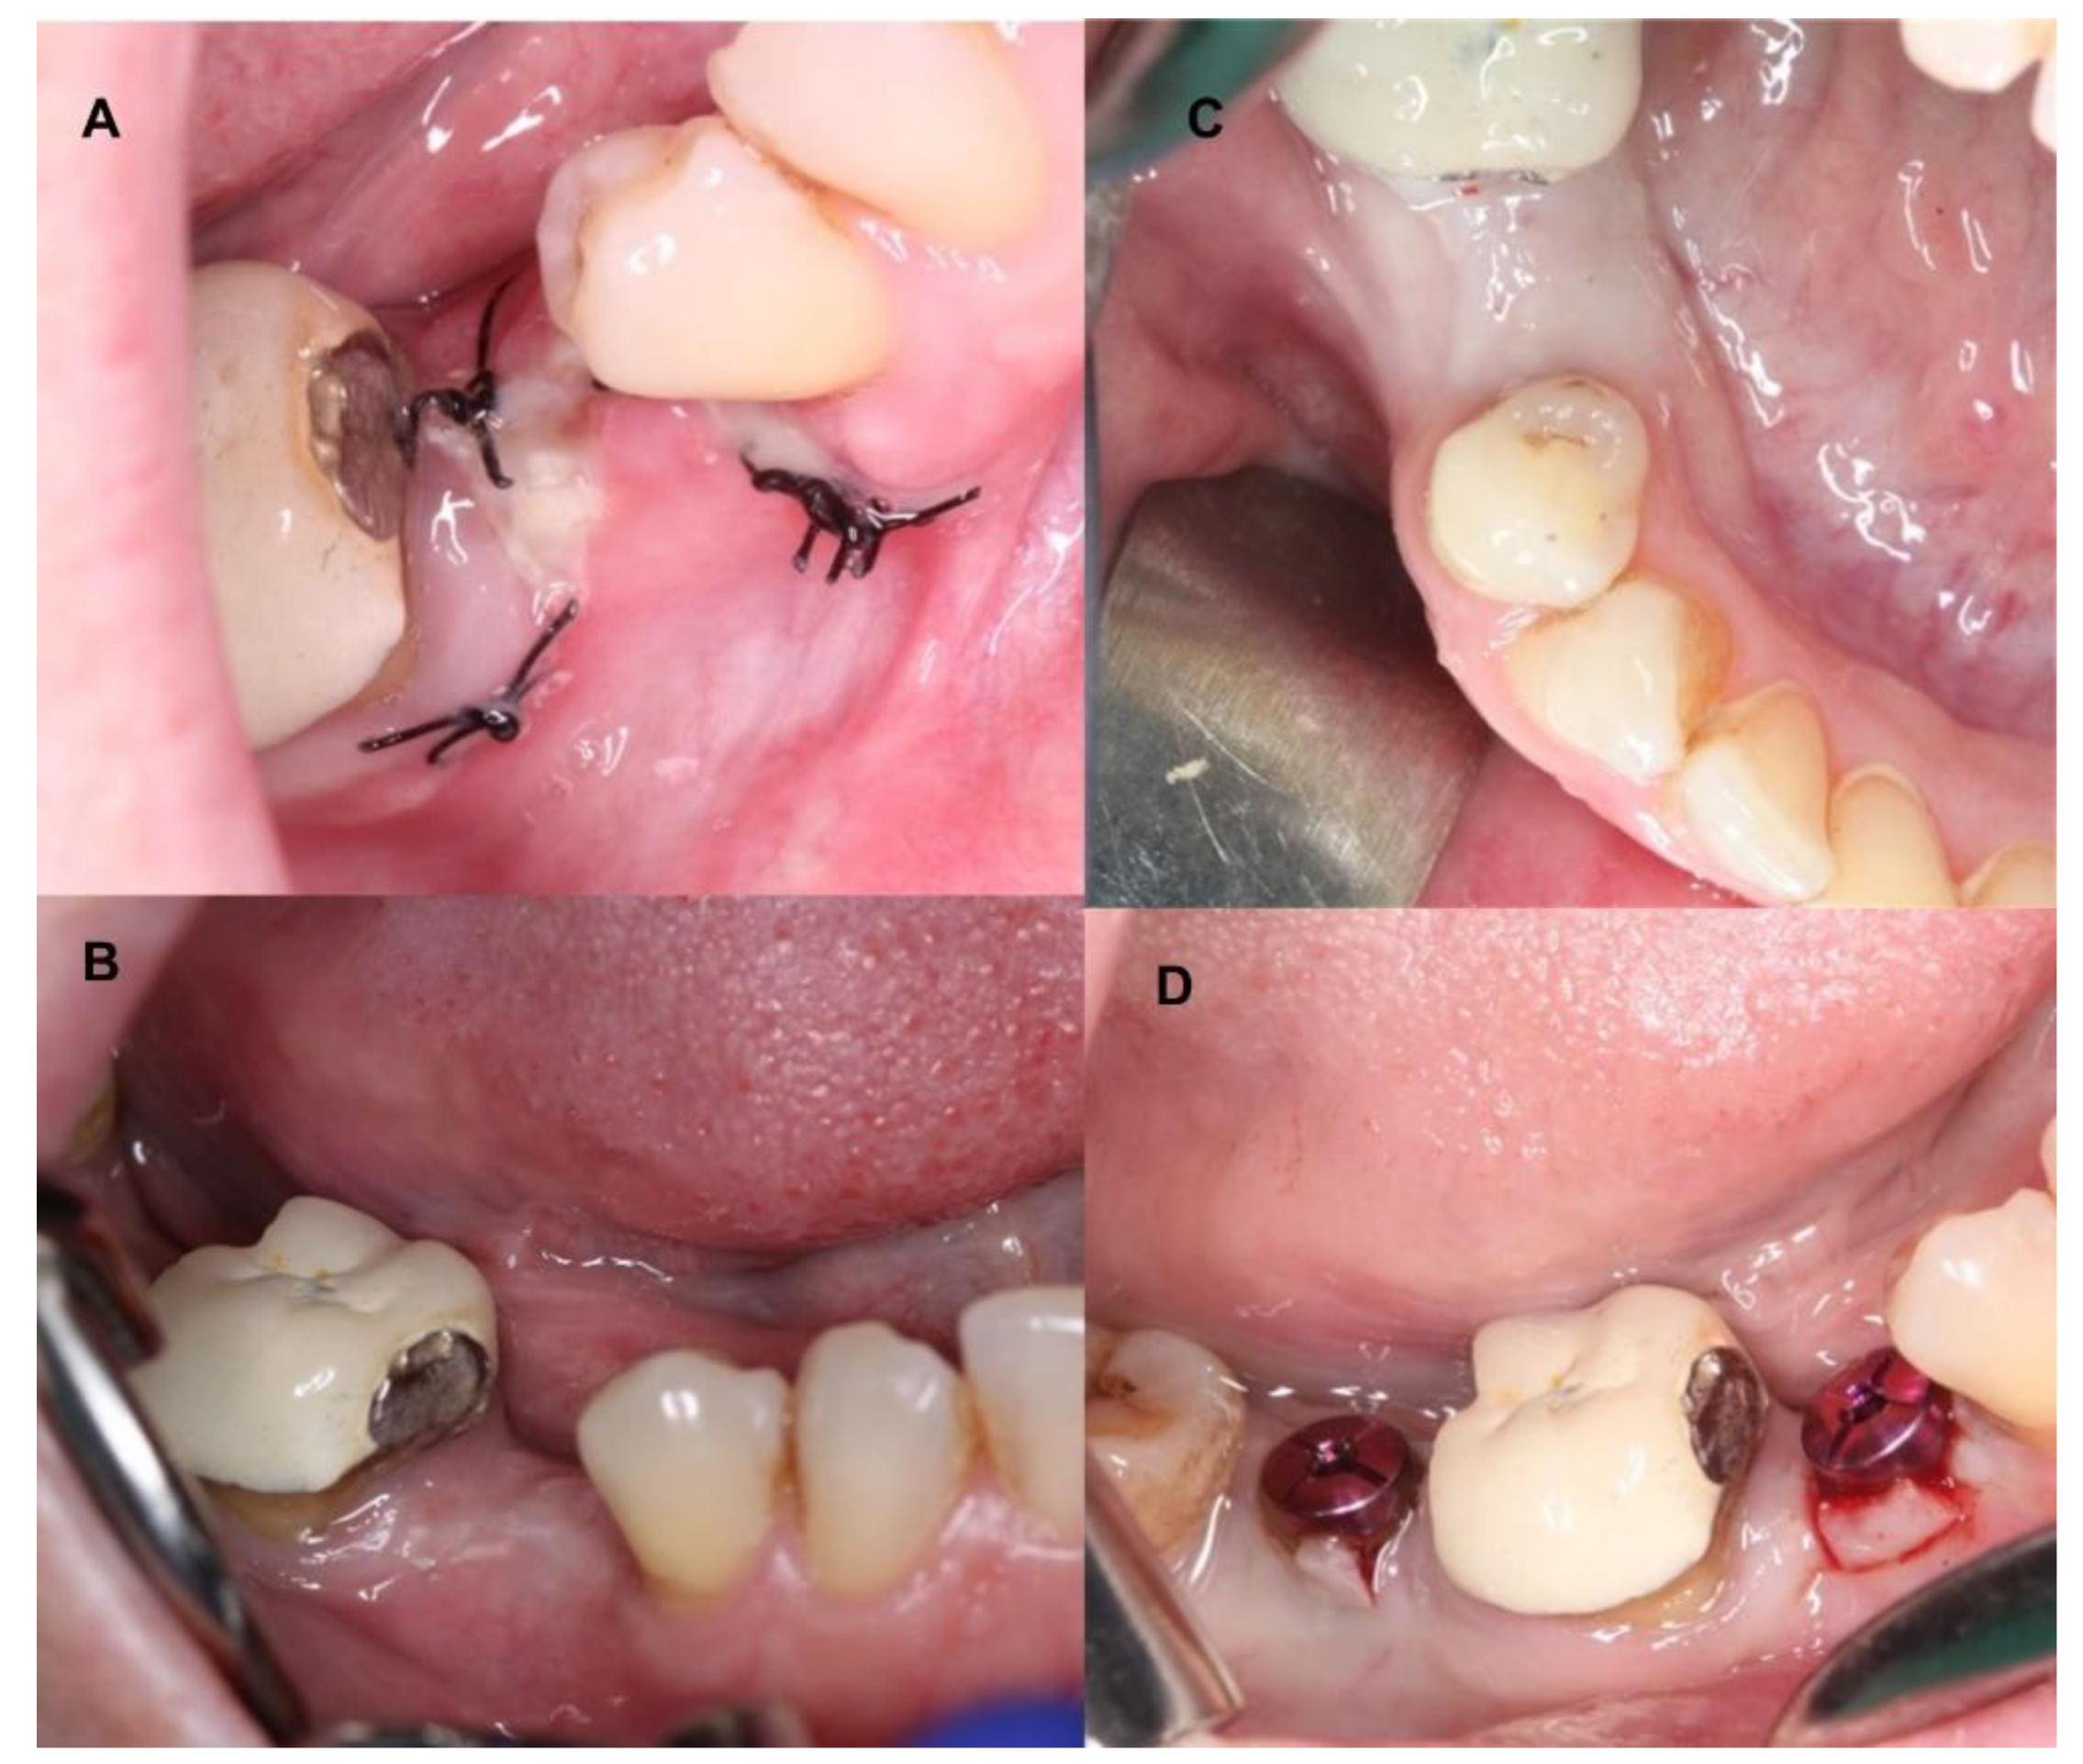

4. Clinical Cases

4.1. Patient No. 1

4.2. Patient No. 2

4.3. Patient No. 3

4.4. Patient No.4

4.5. Patient No.5

4.6. Patient No.6